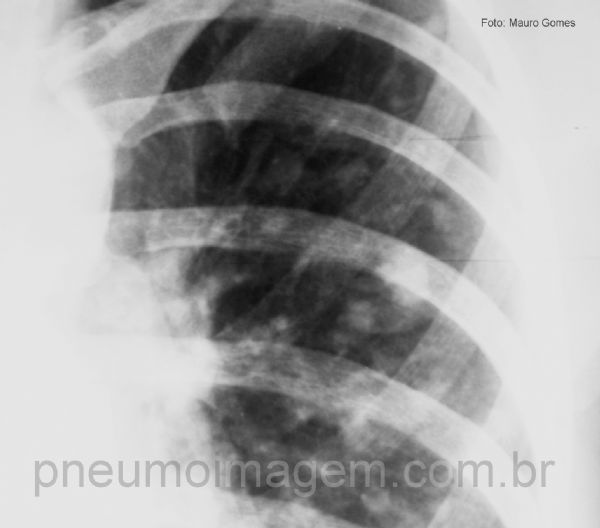

Massa no mediastino que borra o contorno cardíaco à direita, indicando que a lesão deve ser anterior (seta amarela). Há inúmeros nódulos bilaterais (setas pretas) indicando disseminação metastática da doença.

Detalhe do pulmão esquerdo mostrando os numerosos nódulos pulmonares. Dependendo do grau de diferenciação neural, esses tumores são denominados Sarcoma de Ewing, quando é um tumor indiferenciado, ou Tumor Neuroectodérmico Primitivo Periférico (PPNET), quando apresenta características de diferenciação neural.

Numerosos nódulos bilaterais. Observe que há íntimo contato do nódulo com o vaso adjacente (seta amarela), indicando disseminação hematogênica da doença.